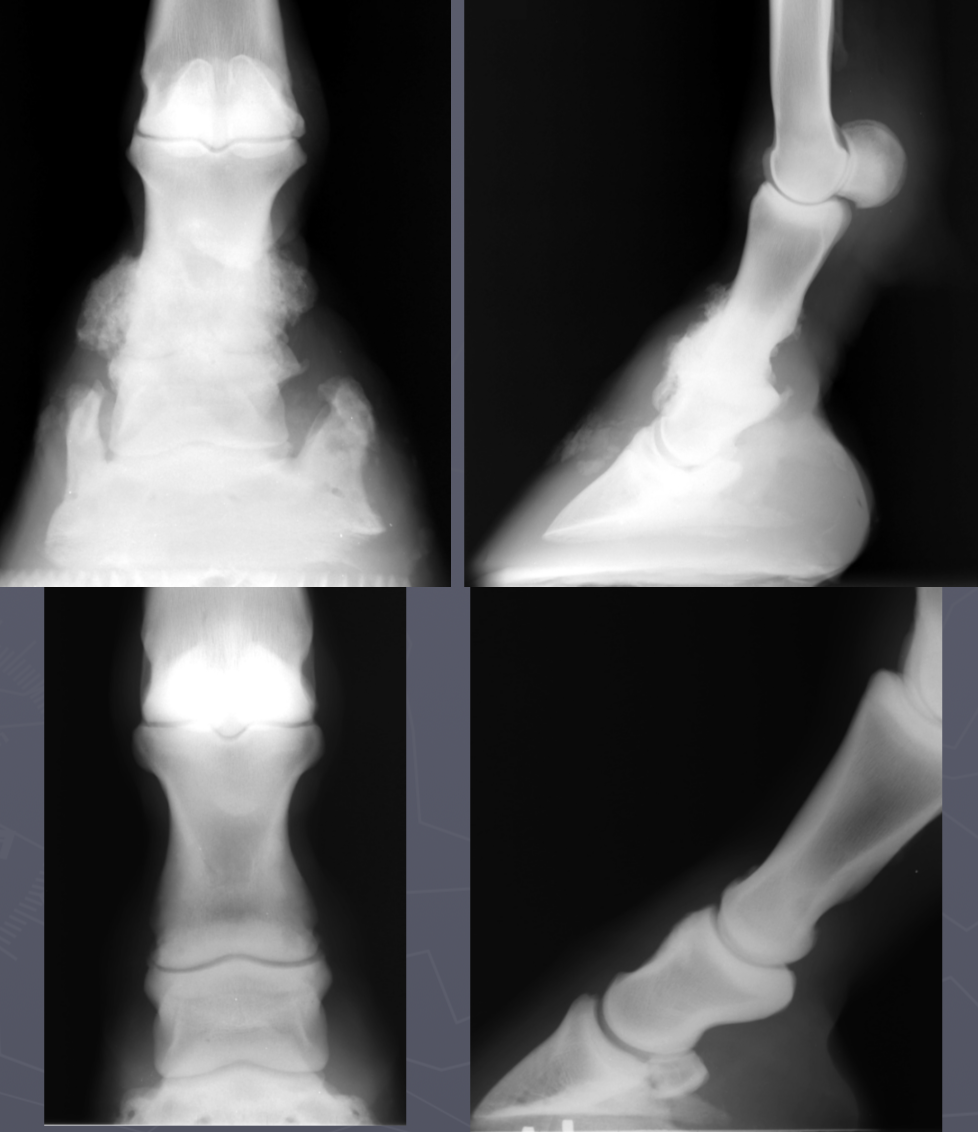

primary bone tumor